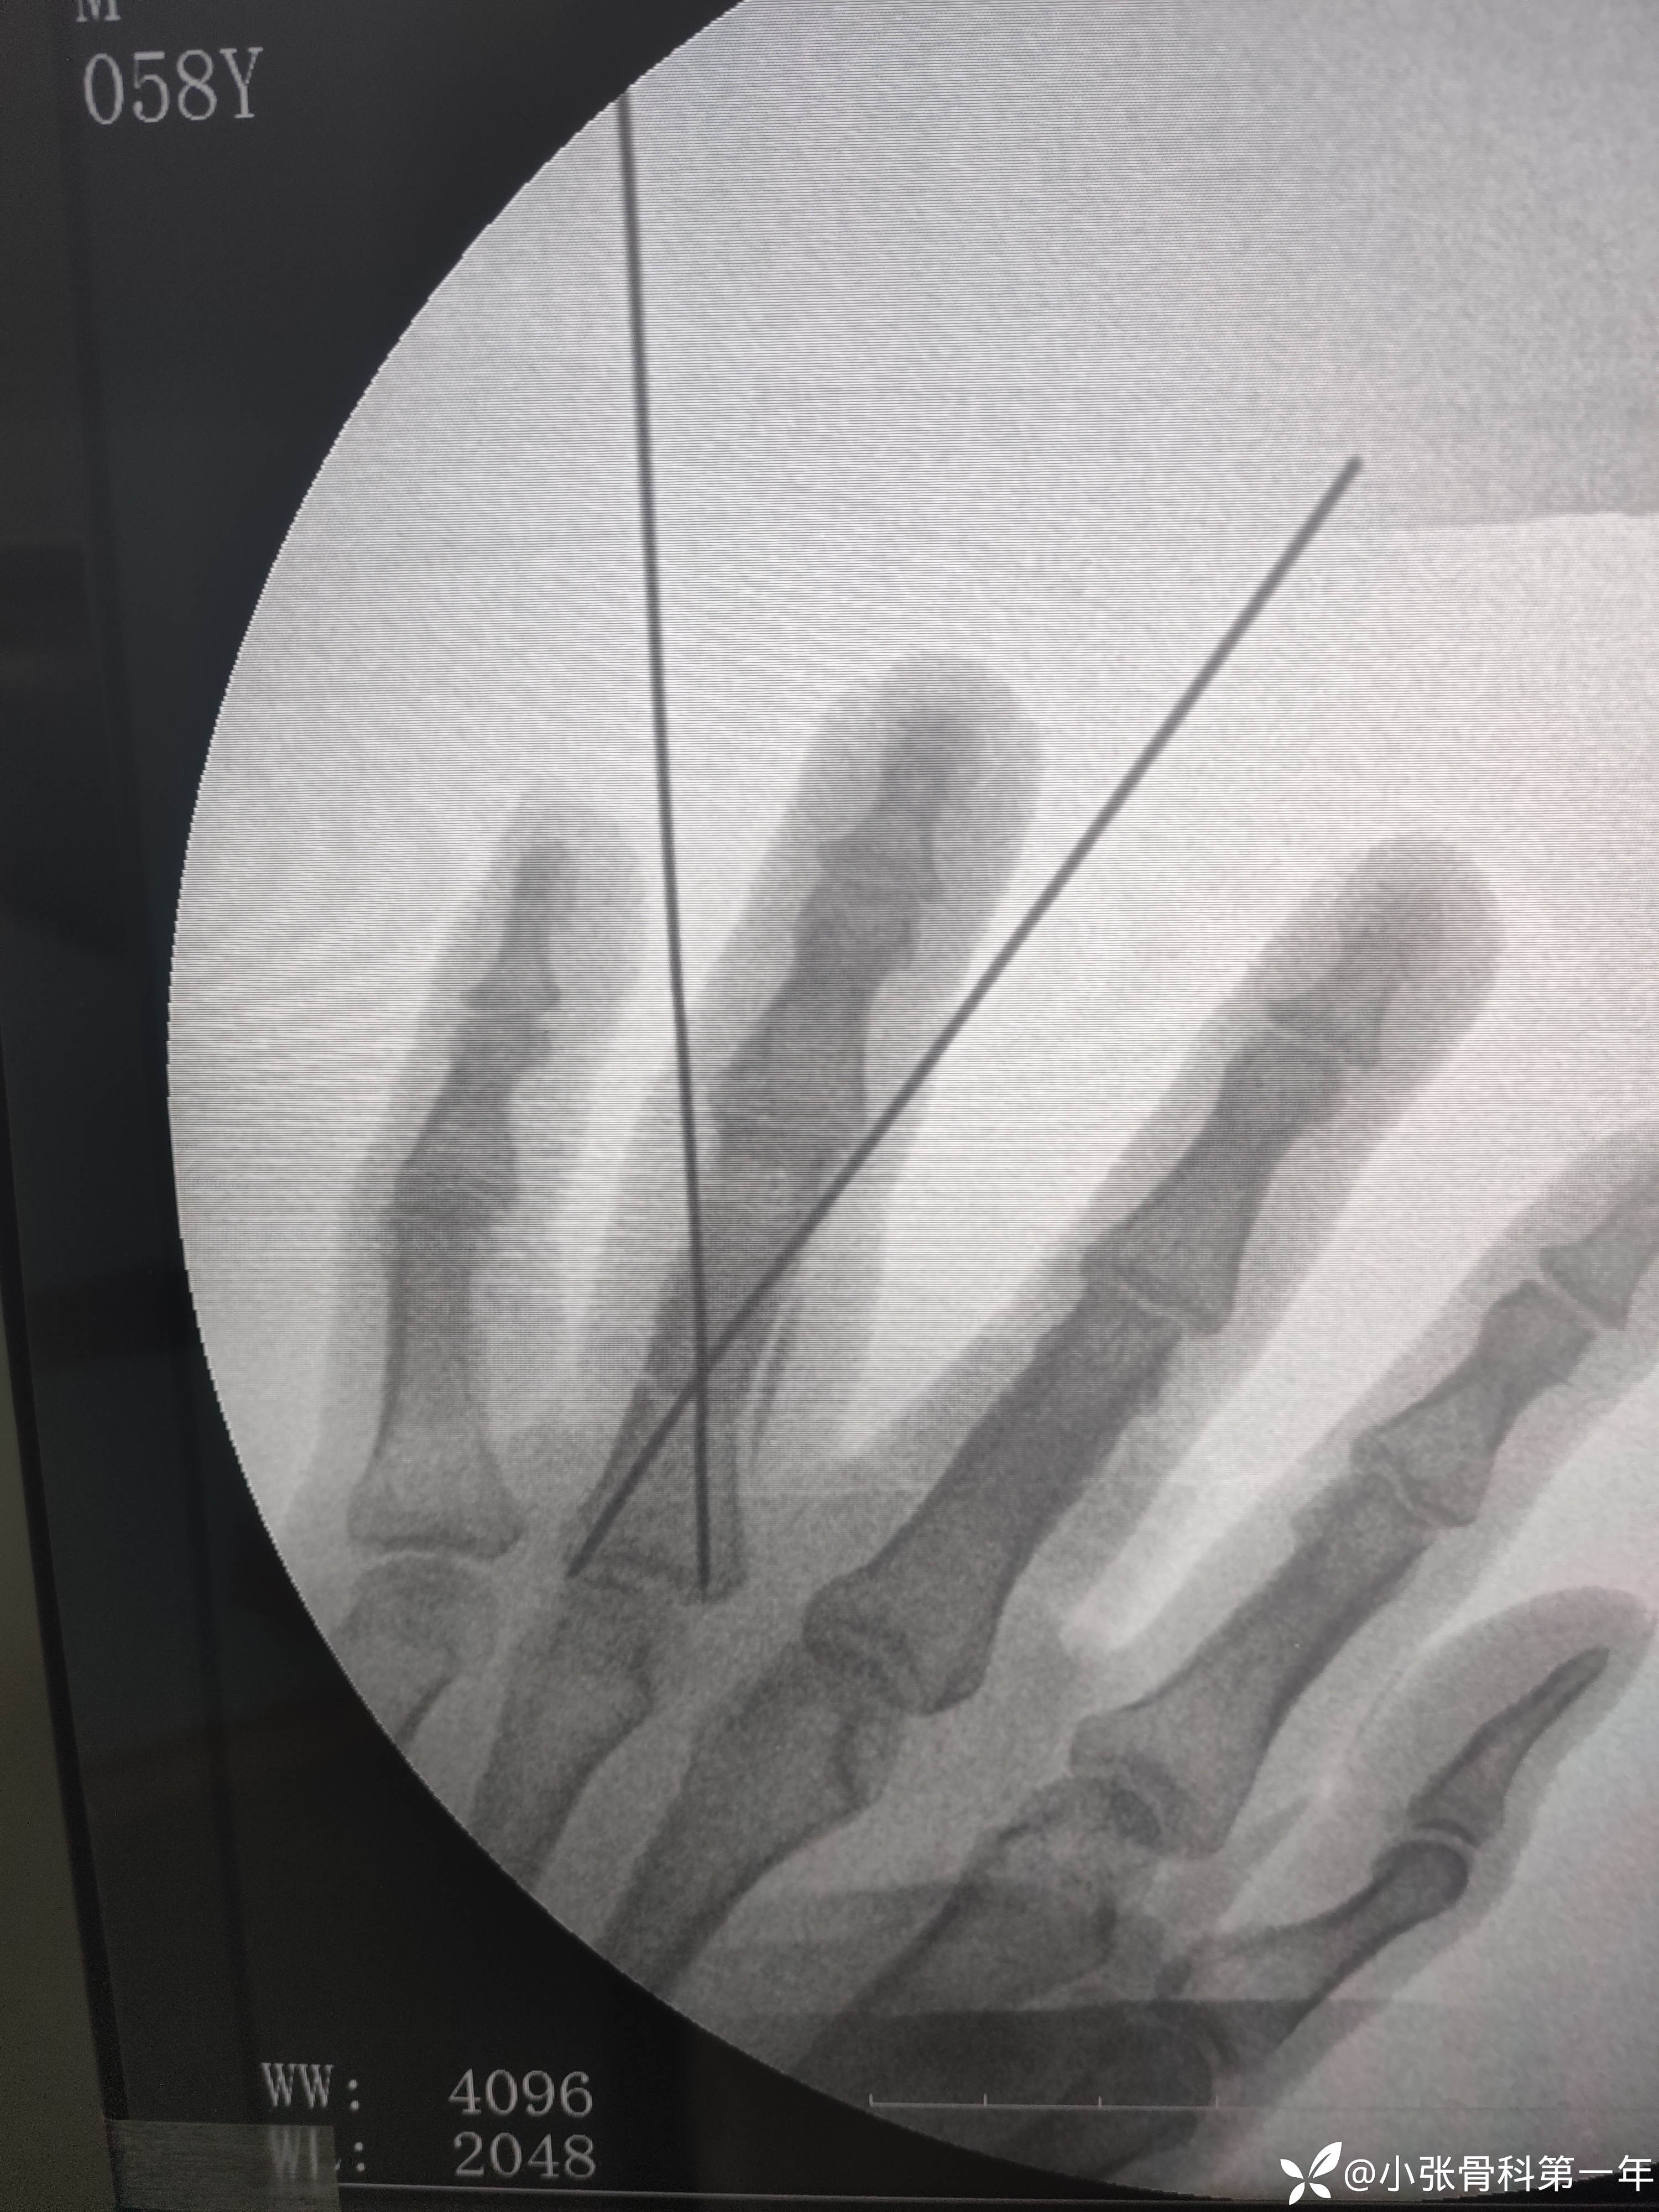

急诊闭合复位克氏针内固定术

用2枚1.2克氏针,第二枚打架,一直过不去,调整角度位置不好,最后换了1.0的一枚,吸取教训了,耽误了半个小时,手术下来心情沉重,以为半小时就ok了,吃一堑长一智。

有老师指骨骨折闭合复位技巧跟克氏针选取指导一下,想学张三版主的克氏针外架,但是心里还是选了传统的交叉克氏针。